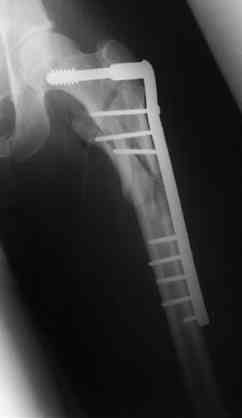

В приложении отправляю послеопер. снимки бедра и лодыжки обсуждаемого вчера больного.